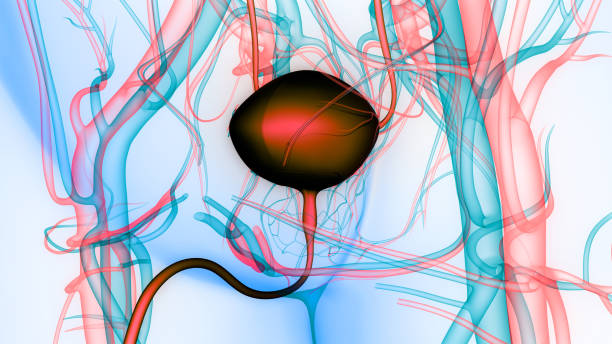

방광암은 방광 내부에 악성 종양이 생긴 것을 말합니다. 이 종양은 방광 벽에서 시작하여 방광 내부로 침입할 수 있으며, 심각한 경우 다른 조직이나 기관에도 전이될 수 있습니다.

방광암은 다양한 원인에 의해 발생할 수 있습니다. 그 중 가장 일반적인 원인은 담배 흡연입니다. 담배에는 암을 일으키는 수많은 화학물질이 포함되어 있으며, 방광 내부에 직접적으로 노출되면 방광암 발생의 위험이 크게 증가합니다. 또한 방광암은 유전적인 요인과 환경적인 요인(토양 오염, 화학 물질 노출 등)에 의해 발생할 수 있습니다.